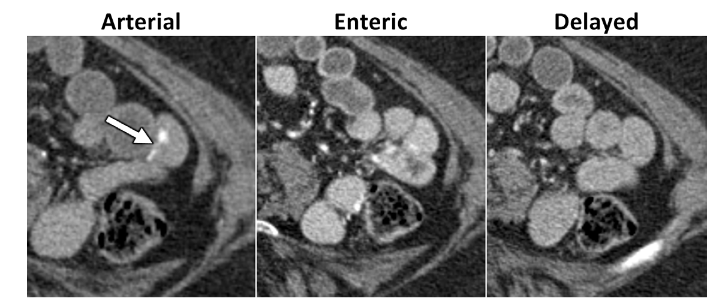

CT Enterography (uses oral contrast). Technique: CTE should be performed using multiphase technique in patients older than 40 years of age where vascular lesions are a common cause for bleeding.